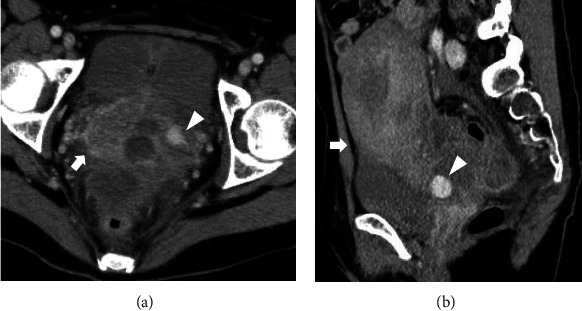

子宫动脉假性动脉瘤(UAP)是妊娠和产后危及生命的并发症。由于没有阴道出血,外生性UAP破裂的早期诊断是困难的。本研究报告了一例31岁的产后妇女,阴道分娩后7天出现腹痛和发烧,无产妇休克症状。超声检查显示外生性UAP破裂伴腹膜出血,经计算机断层扫描证实。介入放射学证实假性动脉瘤位于子宫动脉分叉处,诊断后立即用线圈和正丁-2-氰基丙烯酸酯栓塞。患者症状缓解,栓塞12天后出院。产后8个月,经阴道超声检查未见UAP。即使没有特定的危险因素,如剖宫产或子宫内膜异位症,外生性子宫内膜异位症也可能发生,而且子宫内膜异位症不一定在分娩后立即破裂。产科医生必须保持警惕外源性UAP破裂的可能性,表现为腹痛和产后发烧,而不是不稳定的生命体征。这是首次报道发生在子宫动脉分叉水平的外生性UAP。确定外生性UAP可能发生的部位有助于该病的早期诊断。

A uterine artery pseudoaneurysm (UAP) is a life-threatening complication during pregnancy and postpartum. Early diagnosis of exophytic UAP rupture is difficult due to the absence of vaginal bleeding. This study reports the case of a 31-year-old postpartum woman who presented with abdominal pain and fever seven days after vaginal delivery, without symptoms of maternal shock. Ultrasonography revealed a ruptured exophytic UAP with hemoperitoneum, which was confirmed using computed tomography. Interventional radiology confirmed that the site of the pseudoaneurysm was at the level of the uterine artery bifurcation, and embolization was performed immediately after diagnosis using a coil and n-butyl-2-cyanoacrylate. The patient's symptoms were relieved, and she was discharged 12 days after the embolization. At eight months postpartum, the UAP was not visible on transvaginal ultrasonography. Exophytic UAP can occur even in the absence of specific risk factors such as cesarean section or endometriosis, and the UAP may not necessarily rupture immediately after delivery. Obstetricians must remain aware of the possibility of exophytic UAP rupture manifesting as abdominal pain with postpartum fever, rather than as unstable vital signs. This is the first report of an exophytic UAP that occurred at the level of the uterine artery bifurcation. Identification of the sites where exophytic UAP can occur can aid in the early diagnosis of the condition.